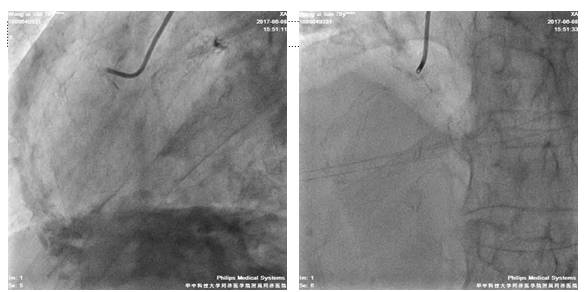

四日后,尝试左冠PCI术

股动脉路径

7F EBU3.5/GC

Runthrough NS,ASAHI SION,BMW导丝

2.5*20mm球囊扩张LAD10*12atm

先后与LAD远段-近段置入2.5*33mm、2.75*33mm、3.0*29mm DES支架,三支架串联